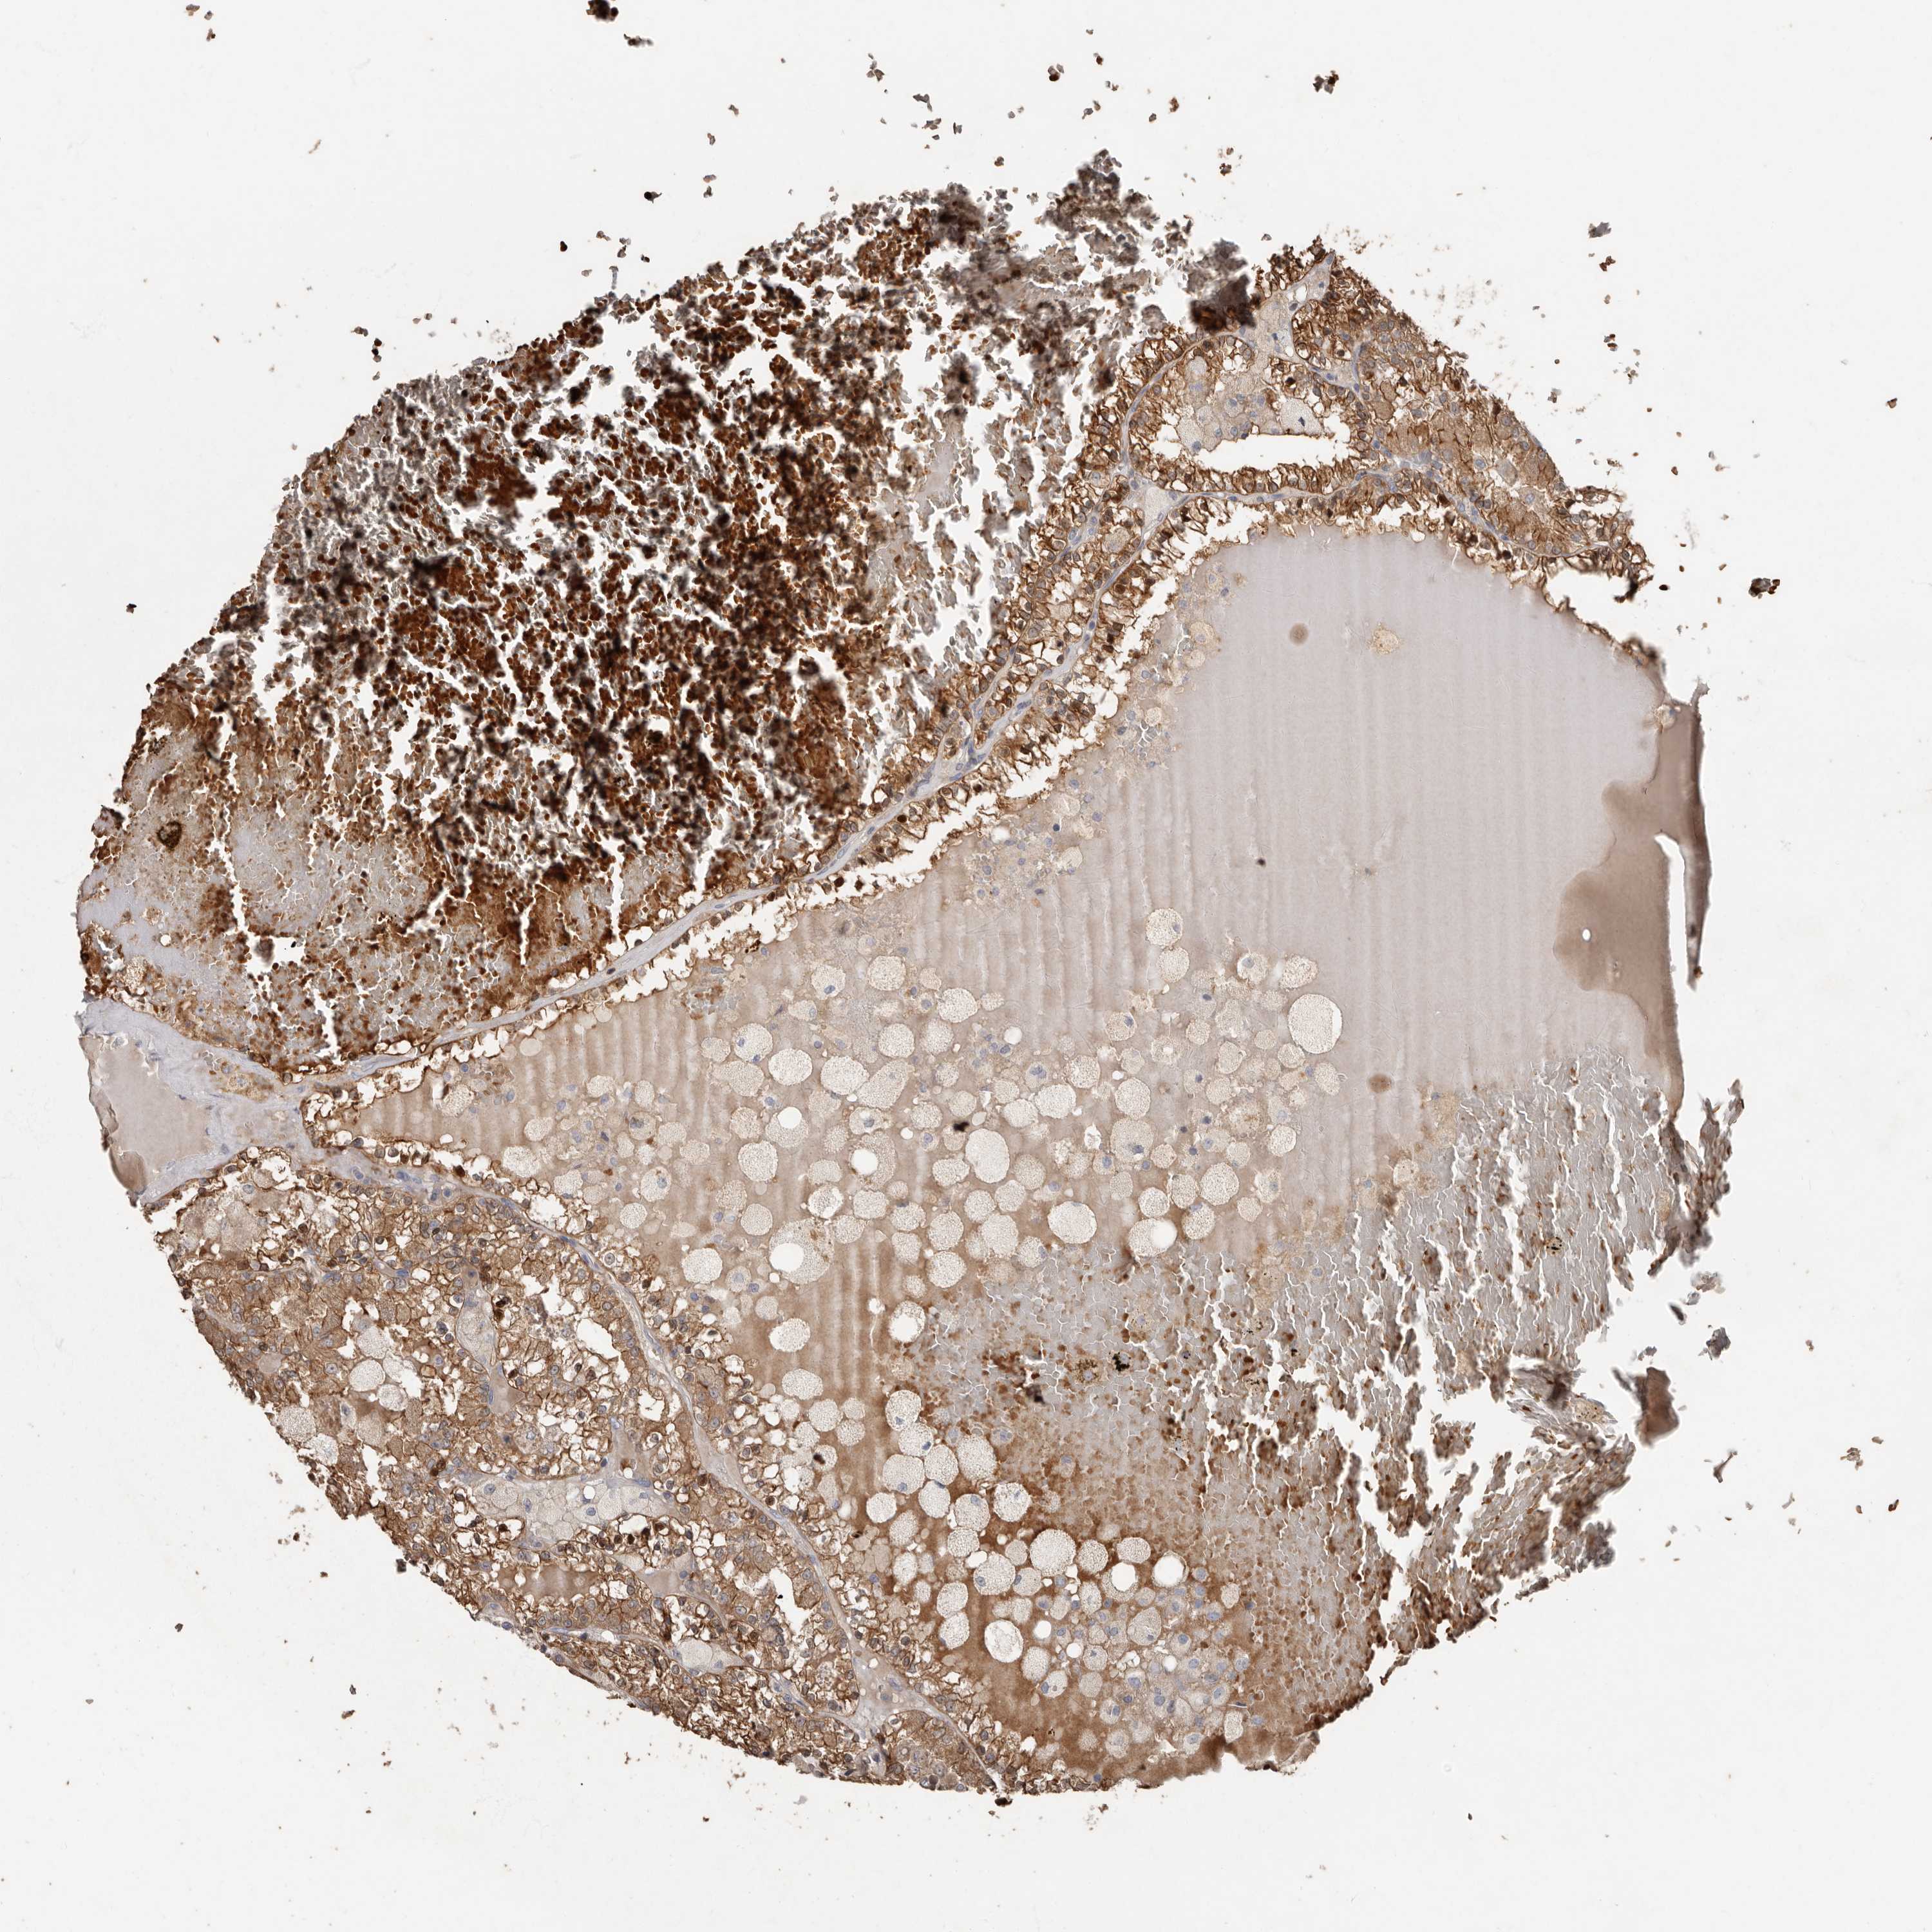

CANCER RENAL CANCER Show tissue menu

KICH TCGA KIRC TCGA KIRC VALIDATION KIRP TCGA PROTEIN RCC CPTAC PROTEIN EXPRESSION